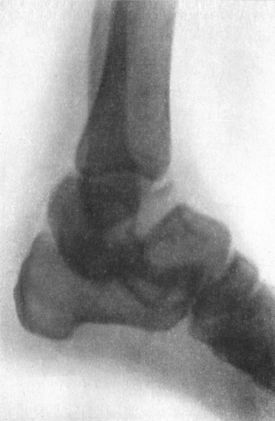

| 93. | Section through Ankle-joint showing relation of Epiphyses to Synovial Cavity | 186 |

| 94. | Radiogram of Pott's Fracture, with Lateral Displacement of Foot | 187 |